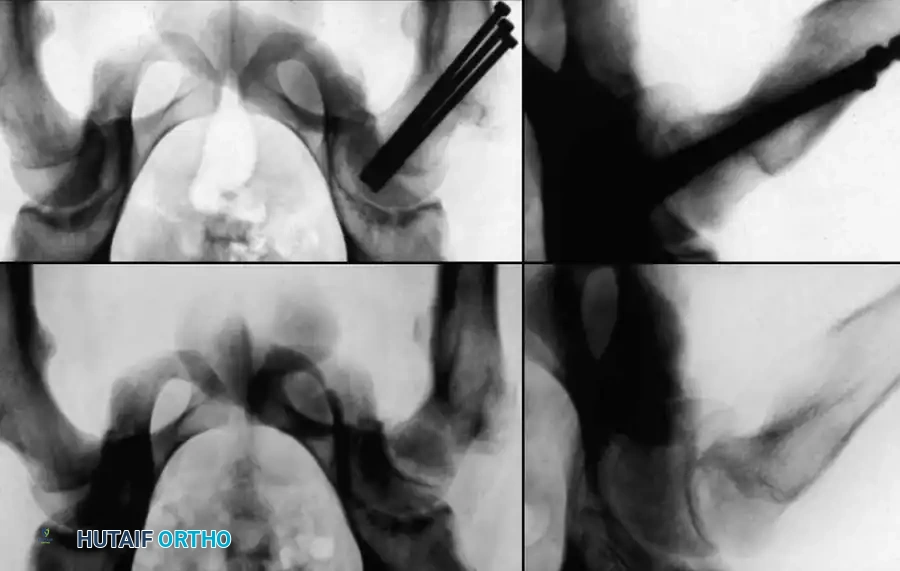

2. Fluoroscopic Setup and the "Rotating Beam" Technique

In situ pinning is fundamentally a radiographic technique. Menche, Lehman, Rab, Moseley, and Morrissy have all emphasized the absolute necessity of a rotating fluoroscopic beam.

The C-arm must be able to rotate freely through a 90-degree arc from the AP to the true lateral position without moving the patient's leg.

3. Guidewire Placement: The Morrissy Principles

Morrissy identified two common errors in SCFE pinning:

1. Passing the pin obliquely toward the anterior surface rather than the center of the head.

2. Passing the pin out the posterior neck and into the head.

To avoid this, the starting point must be selected based on the position of the displaced femoral head. The guidewire must enter the femoral neck so that it crosses the physis perpendicular to its surface and anchors in the exact center of the epiphysis.

* Because the head slips posteriorly, the starting point on the lateral cortex must move anteriorly. The more severe the slip,

Associated Surgical & Radiographic Imaging